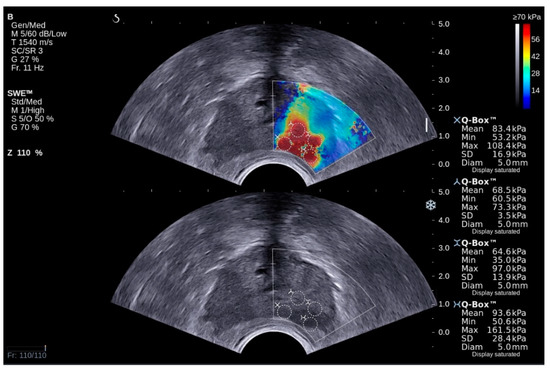

3.1. Methodology for Elastography